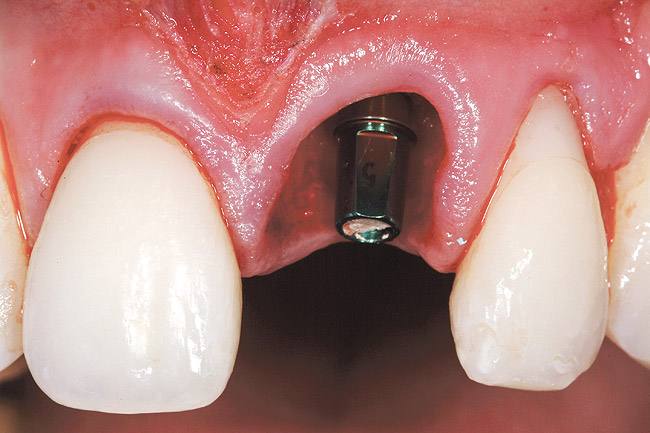

The patient opted for the third option. After administration of an appropriate local anesthetic, a frenectomy was performed using a Nd:Yag laser. This would allow for the loosening of the facial tissues and the coronal repositioning of the pouch at the termination of the procedure. After the frenectomy, the left central incisor was removed by an atraumatic technique preserving the soft tissue emergence profile (Figure 23). Debridement of the extraction socket preceded atraumatic site preparation techniques. A 3.5-mm diameter by 13-mm tapered implant (Prima Connect, Keystone Dental, www.keystonedental.com) was placed to the appropriate depth measurements planned.38,39

After placement of the graft complex, a titanium abutment with a 1-mm collar (Quick abutment, Keystone Dental) was seated and hand-tightened (Figure 25). Retrofitting of the natural tooth shell preserving the pre-existing contact point relationships and line-angle positioning was accomplished from a pretreatment incisal edge registration. The final provisional restoration can be seen in Figure 26.

Figure 25  Case Three Titanium abutment seated

Figure 25

Figure 26  Case Three Immediate provisional restoration.

Figure 26